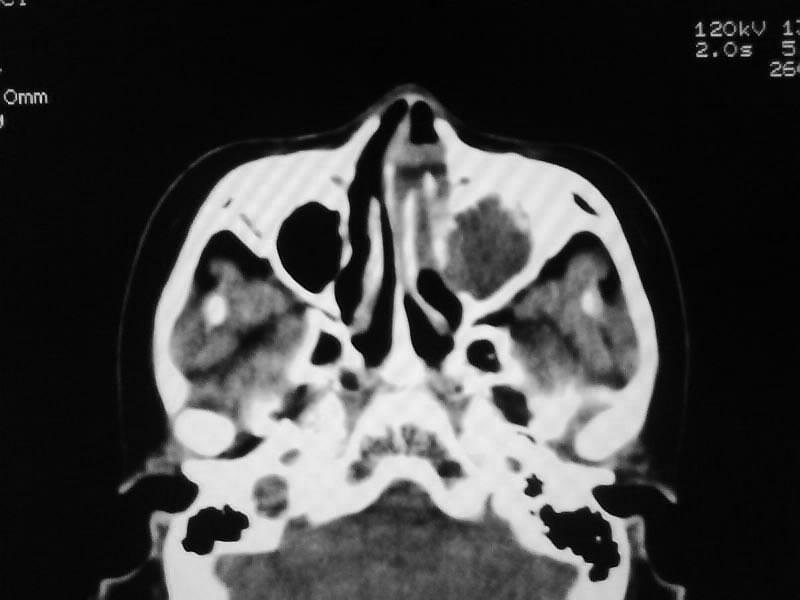

以下是引用zjzjr在2009-5-3 9:59:00的发言:[br]左侧鼻腔息肉、左侧筛窦、上颌窦炎症。双侧下鼻甲粘膜肥厚。

以下是引用随光逐影在2009-5-3 13:02:00的发言:[br]1)左侧鼻腔新生物(息肉可能)。2)左侧上颌窦及左侧筛窦炎症。3)双侧下鼻甲黏膜肥厚。